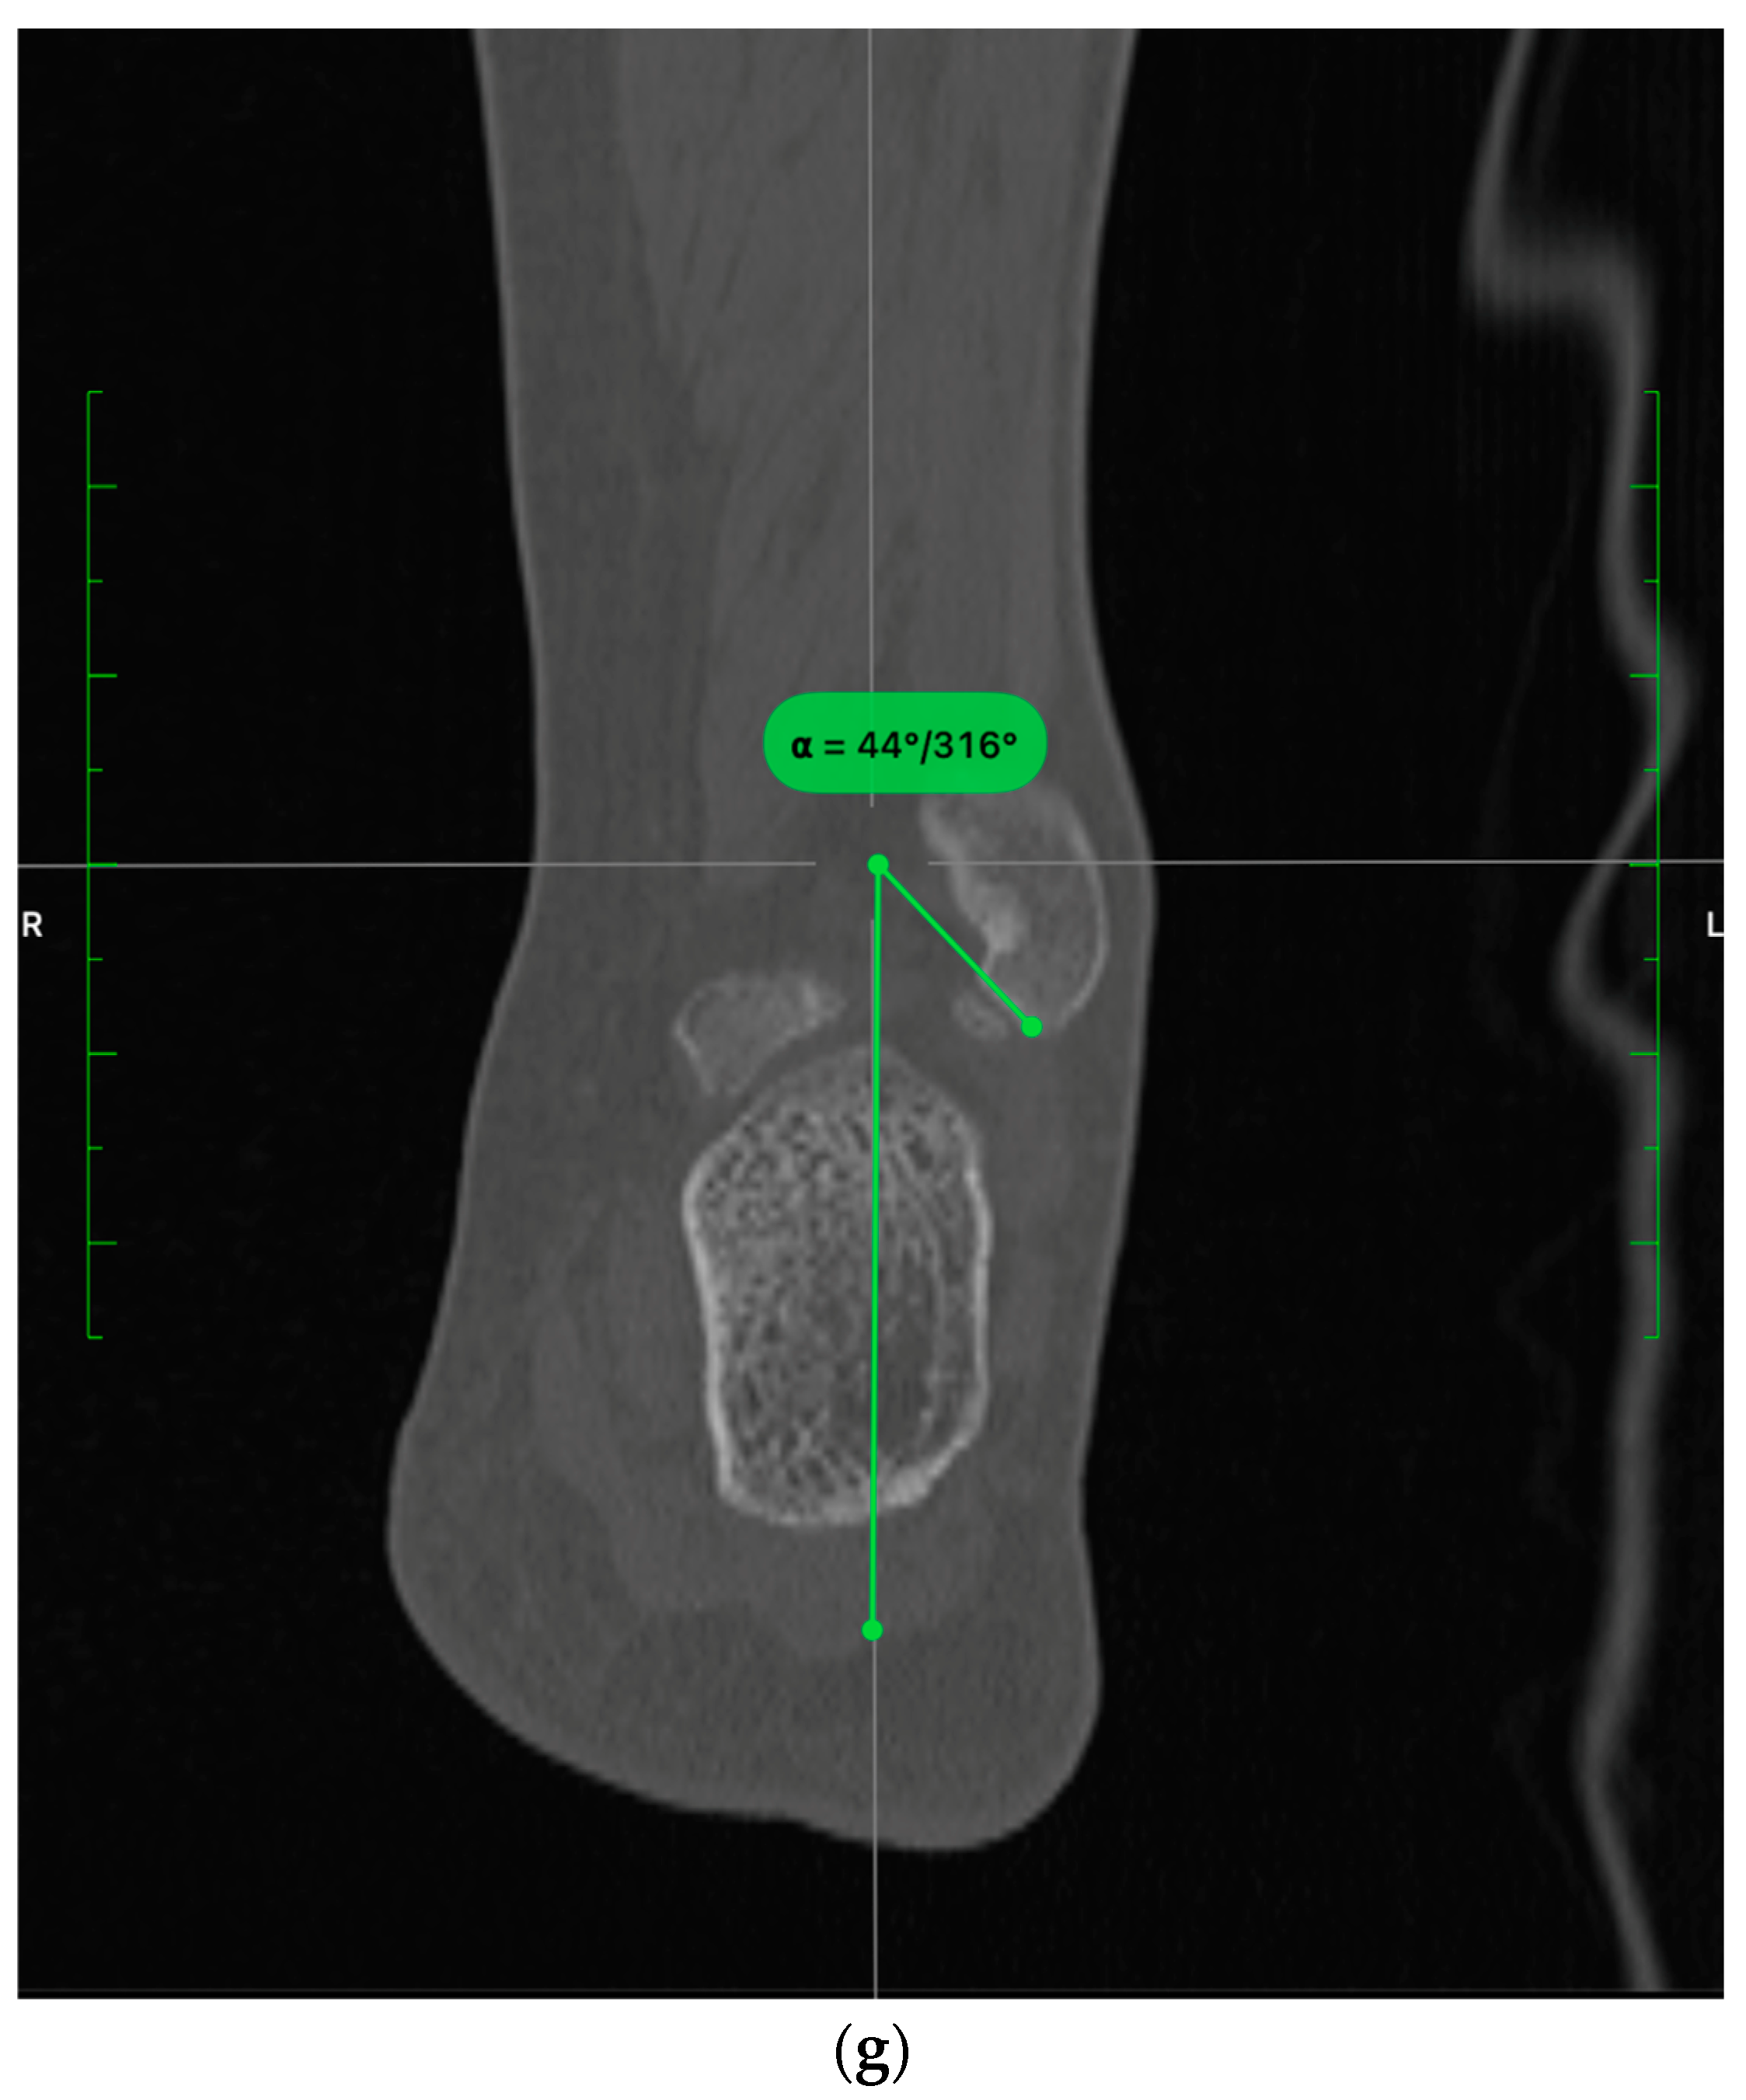

- In the sagittal plane, the lateral malleolus cartilage was fixed as anteriorly as the anterolateral tibial plafond cartilage (restoring the sagittal translation) (Figure 3)

3.2. CT Evaluation